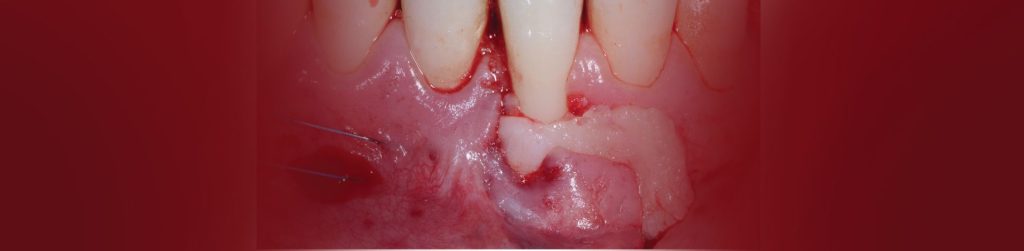

בסמוך למרפאתנו הקמנו חדר הרצאות חדשני וייחודי. ייעודו של האגף החדש הינו להגשים חלום יקר לליבנו, לממש ולקיים מרכז להכשרה קלינית לרופאים ובהדרכה אישית: A PRIVATE ACADEMY. במרכז יתקיימו הרצאות, קורסים עיוניים ומעשיים בהם תהיה צפייה בניתוחים בשידור חי, מחדר הניתוח בזכות מיטב הטכנולוגיה החדשנית. במתחם החדש, אנו נארגן מגוון רב של פעילויות, ומאמינים כי ביכולתנו לתרום מניסיוננו לטובת ציבור רופאי השיניים הכלליים. הקורסים מיועדים לכלל ציבור רופאי השיניים המעוניינים להעשיר את בסיס הידע ואת יכולתם הקלינית בתחומים שונים (פריודונטיה, אימפלנטולוגיה ואסתטיקה), דבר שישרת אותם במרפאתם. המרצים יהיו רופאי המרפאה יחד עם רופאים בכירים ומומחים נוספים אשר יצטרפו לצוות.